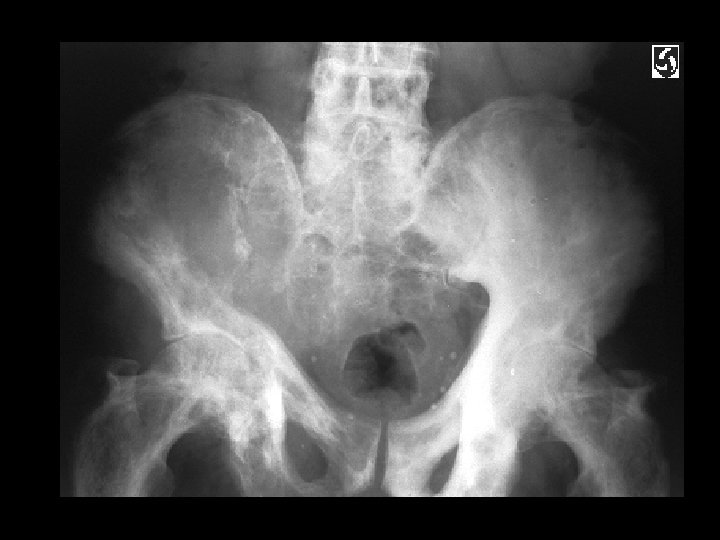

Ankylosing Spondylitis • • Findings: – fused SI joints – right hip erosions – lumbar syndesmophytes Sero-negative chronic inflammatory disease Starts in the low back and progesses upward ddx (sacroilitis) – bilateral • ank spond • IBD – Unilateral • Reiter’s • psoriasis